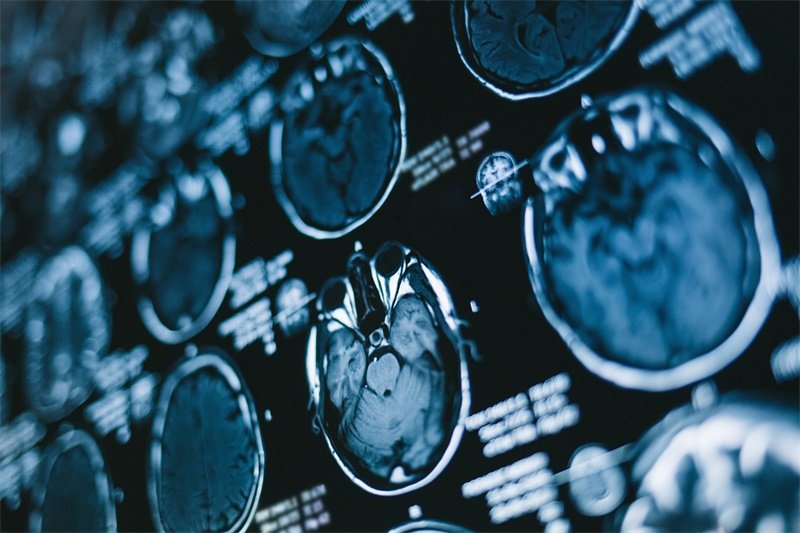

诊断关键技术

影像学检查组合

MRI多序列扫描

T1增强显示肿瘤边界

DWI鉴别脓肿与肿瘤

准确率超过90%

CT三维重建

清晰呈现骨质破坏

脊索瘤典型呈"蜂窝状"